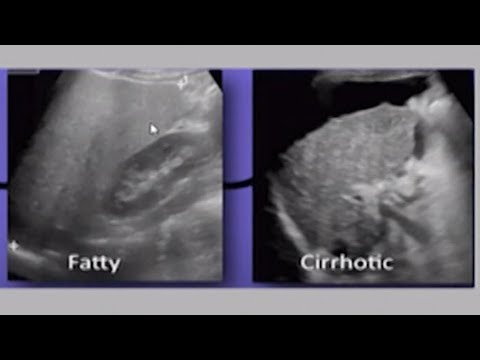

Днес ще ти разкажа за черния дроб. Толкова сложен орган е той и толкова необятна е информацията за него. Останете и ще разберете защо! Не забравяй, че можеш да ме откриеш тук ежеседмично. Всяка сряда съм с теб и с твоето здраве! :) -------------------------- ТЕМИ ► 0:18 Орган и заболявания 2:25 Симптоми 3:22 Профилактика 5:21 Диагноза 8:35 Нашето решение -------------------------- 🔔 АБОНИРАЙ СЕ ► http://www.youtube.com/c/Мин